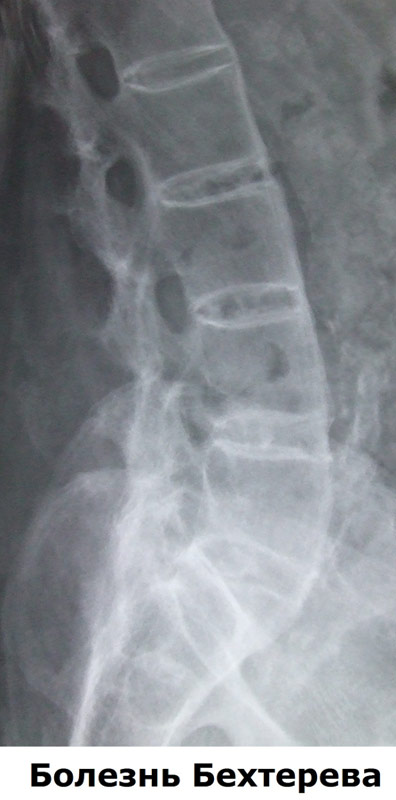

Болезнь Бехтерева

(анкилозирующий спондилоартрит)

- Рентген или другие лучевые методы диагностики. Рентген позволит врачу выявить изменения, произошедшие в суставах и костях, хотя характерные последствия анкилозирующего спондилита могут быть и не видны в начале заболевания. Также могут быть назначены другие исследования, такие как компьютерная томография (КТ) или магнитно-резонансная томография (МРТ), чтобы выявить воспаление и другие изменения в ваших суставах.